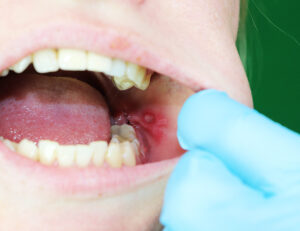

アフタ性口内炎

アフタ性口内炎は、一般的によく見られるタイプの口内炎です。

白くて丸いできものの周囲が赤く縁取られているのが特徴で、睡眠不足やストレス、疲れなどで体の抵抗力が弱まっているときに発生しやすい傾向があります。

一般的にアフタ性口内炎は10日から2週間ほどで自然に治ることが多く、特別な治療を必要としないケースがほとんどです。

ただし、治るまでに時間がかかる場合や、再発を繰り返している場合は、全身性疾患の症状の一部として現れていることもあるため、歯科や口腔外科を受診するようにしましょう。